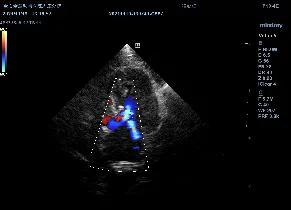

右侧左室流出道观:

左室不均匀性增厚,心尖最为明显。可见乳头肌增大异常,腱索连接异常,室间隔基部异常向左心室内增大,导致左室流出道前窄后宽。左心房主观增大。color模式下收缩期可见左室流出道以红色为主的花色血流信号,左房可见蓝色为主的花色血流信号。